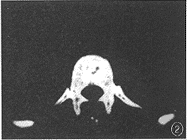

患者男,36岁。腰背部疼痛,颈部不适2个月。因疼痛加重,腰背部出现包块而住院治疗。查体:体温37.5℃,身体消瘦,痛苦病容。T12棘突两侧有直径4cm大小包块,有波动,压痛。T6棘突左侧软组织隆起,压痛。颈部压痛,活动轻度受限,四肢活动及大小便正常。血沉:46mm/h。胸片显示:粟粒型肺结核。颈椎摄片:未见异常。X线片示:T6左侧椎弓根破坏。CT片示:T6左侧椎板、椎弓根骨质破坏,有死骨,且有软组织肿胀影突入椎管(图1)。T12棘突骨质破坏,有死骨,后方皮下有低密度影(图2)。诊断:T6、T12附件结核伴冷脓肿,粟粒型肺结核,颈痛待查。按3HRZS/15HR方案抗痨治疗[1,2](注:H-异烟肼,R-利福平,Z-吡嗪酰胺,S-链霉素)。半个月后,分别行T6和T12经后路结核病灶清除术,清除较多脓液、干酪样物及少量死骨。病理检查:T6、T12结核。术后10余天,颈痛加重,活动受限,吞咽感咽部不适,有发热、出汗,体温38℃。颈椎CT片示:寰椎骨质破坏,有死骨,寰枢关节左右间隙不对称,咽后壁软组织影增宽,食管受压(图3,4)。诊断:寰椎结核伴冷脓肿,寰枢椎半脱位。给予输血、补液等支持治疗后,经口腔行病灶清除术,清除少量脓液、干酪样物及少量死骨。术后继续抗痨治疗,颈托固定。此后,颈痛缓解,精神食欲渐好,血沉降至28mm/h。1个月后,胸前(胸骨柄、双侧第四前肋骨处)、上背部出现包块。胸片显示:粟粒型肺结核,双侧第四前肋内侧骨质破坏(图5)。CT片示:T2棘突骨质破坏消失,有低密度的软组织肿胀影(图6)。诊断:T2棘突结核伴冷脓肿,胸骨柄及双侧第四前肋结核伴冷脓肿。考虑结核杆菌感染未能完全控制,改用3HE1321ThK/21HE1321Th方案[1-3](注:H-异烟肼,E-乙胺丁醇,1321Th-丙硫异烟胺,K-卡那霉素)抗痨治疗半个月后,行病灶清除术,分别清除T2、胸骨及肋骨结核病灶。术后1年随访,患者恢复了日常生活及工作,局部无疼痛,血沉正常,体重由入院时的45kg增加到70kg,再未发现新的结核病灶。

图1CT片显示T6左侧椎板、椎弓根骨质破坏,有死骨,且有软组织肿胀影突入椎管图2CT片显示T12棘突骨质破坏,有死骨,后方皮下有低密度影图3,4CT片显示寰椎骨质破坏,有死骨,寰枢关节左右间隙不对称,咽后壁软组织影增宽,食管受压图5胸片显示粟粒型肺结核,双侧第四前肋内侧骨质破坏图6CT片显示T2棘突骨质破坏消失,有低密度的软组织肿胀影